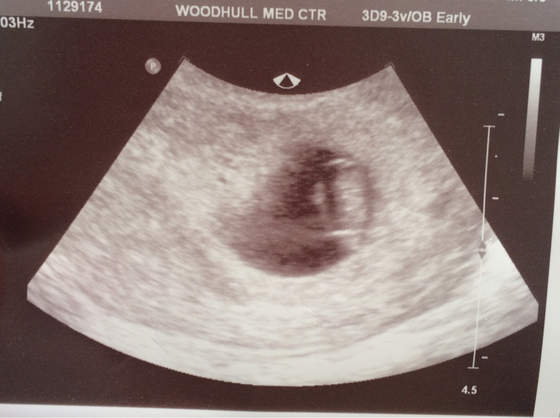

Gratulacje podwójne, bliźniaki to zawsze było moje marzenie